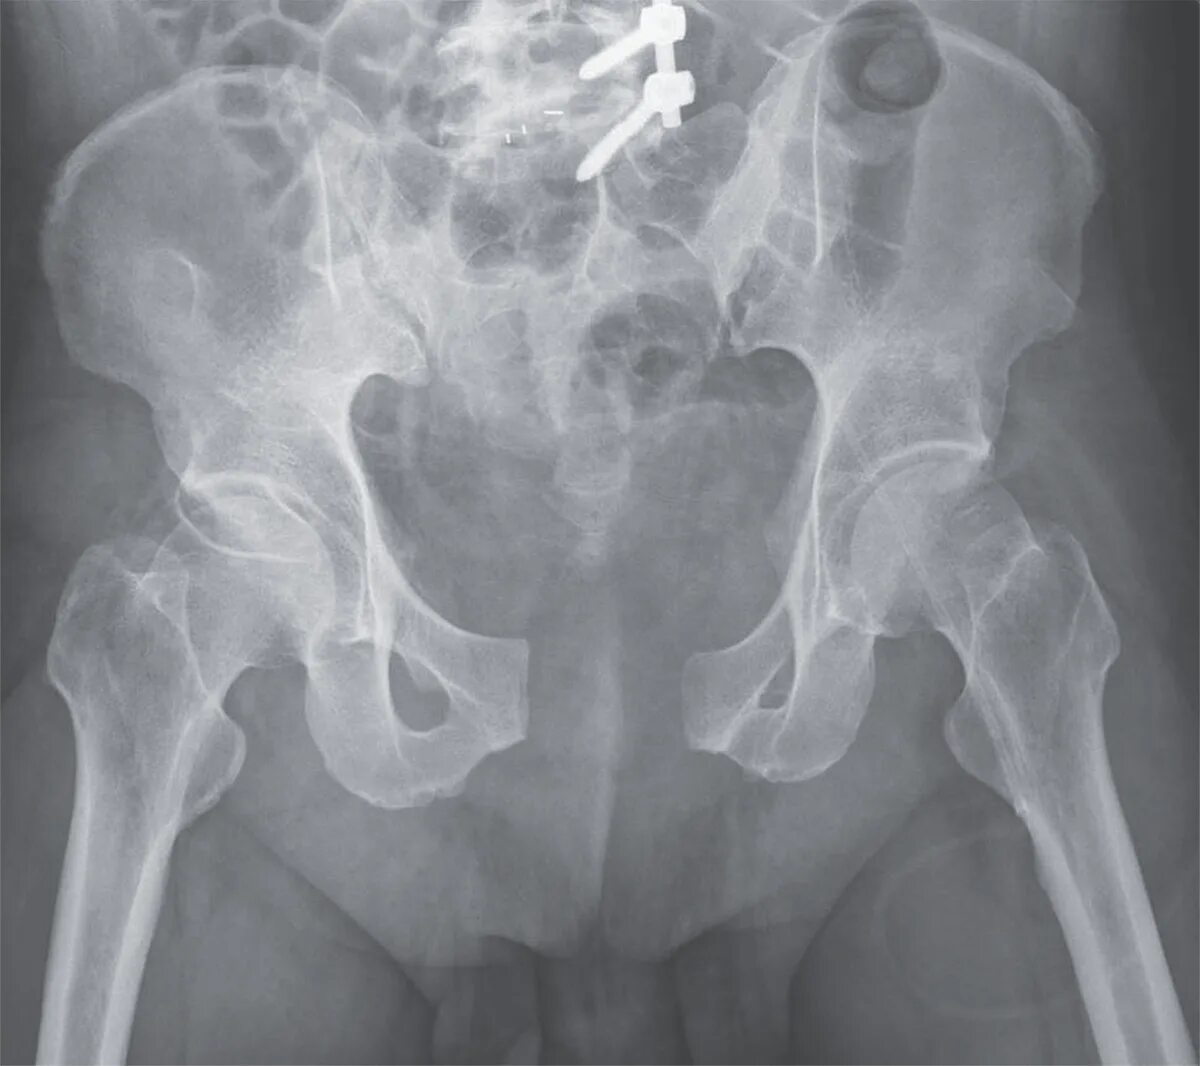

Перелом гребня